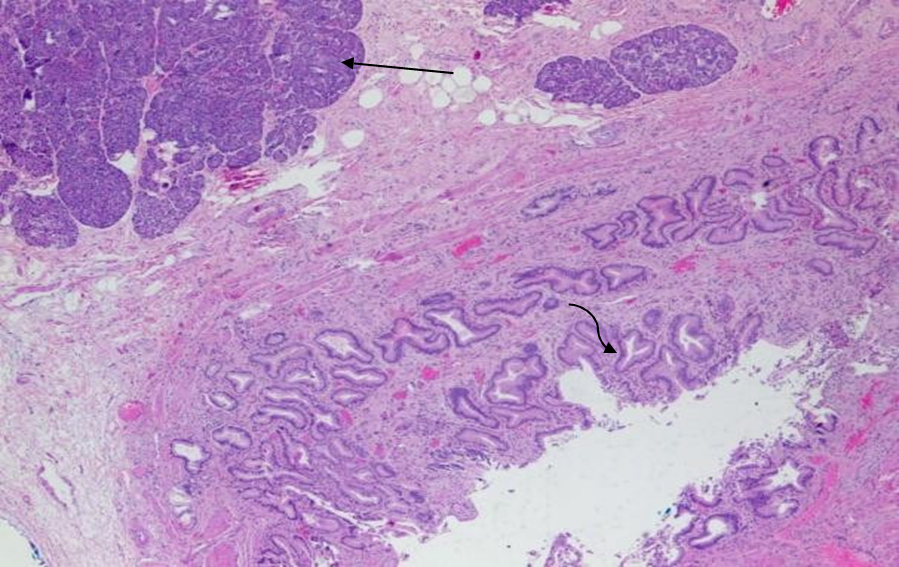

Figure 3 Histopathology of pancreatic heterotopia in the gallbladder of a 51-year-old woman using a hematoxylin and eosin stain demonstrates mucin secreting columnar epithelium lining the cystic duct (curved arrow) and pancreatic tissue (straight arrow). [100x view]